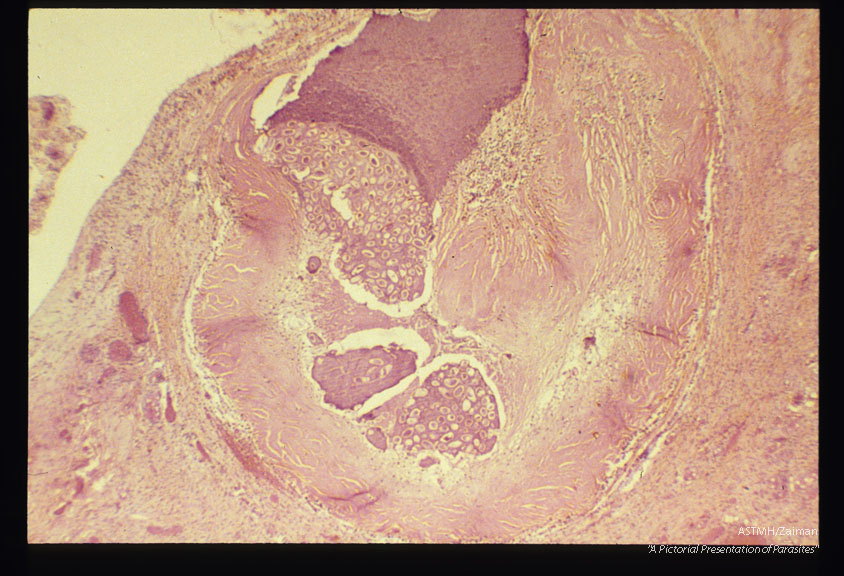

Ovarian enterobiasis.

Enterobius vermicularis

Description: Ovarian enterobiasis.